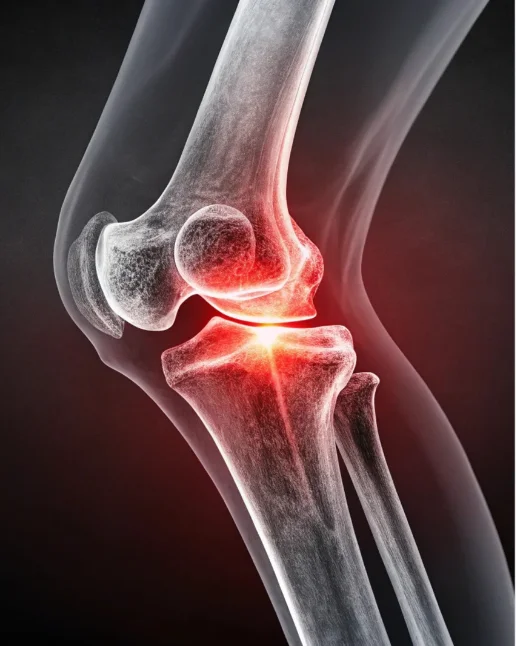

Knee Arthroscopy & Reconstruction

Advanced minimally invasive procedures for ligament injuries, meniscus tears, and cartilage damage. Designed to relieve pain, restore stability, and help you return to an active lifestyle quickly.

Joint Replacement Surgery

Expert in hip, knee, and shoulder joint replacements using modern, minimally invasive techniques for long-lasting mobility and pain-free living.